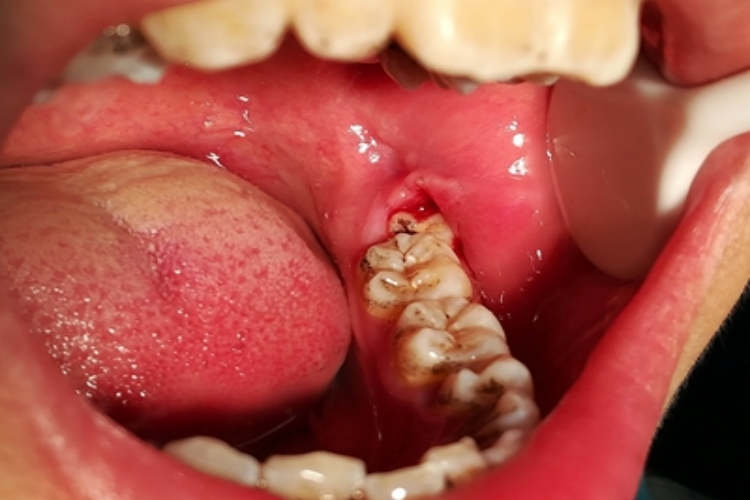

严重智齿冠周炎的患者,临床上可表现为智齿周围牙龈组织红肿、糜烂,还可见位置萌出异常的智齿,症状严重时炎症侵袭咀嚼肌,可导致不同程度的开口受限,有明显触痛,压迫时有脓血液溢出。

智齿在萌出过程中形成与口腔相通的盲袋,盲袋内易存储食物残渣、唾液、细菌,在适宜的口腔温度和湿度环境中很容易滋生细菌,当患者刷牙方法不对,或长期不刷牙,导致口腔卫生差时,极易诱发智齿冠周炎,若不及时治疗,病情会逐渐加重。